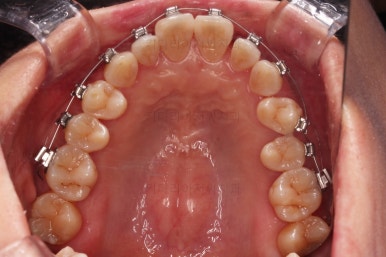

초진 시, 입안의 모습이에요.

"최근 들어 점점 틀어지고, 점점 튀어나오고, 점점 사이가 벌어져요."

이번에 사용하신 장치는 엠파워 메탈이라고 하는 자가결찰 금속 장치인데요.

금속 재료를 시각적으로 신경쓰지 않으셔꼬 메탈장치가 세라믹에 비해 양치라던지 잇몸에 그래도 약간의 장점이 있어서 추천되기도 했어요.

비발치 치료에서 핵심되는 장치가 미니스크류에요.

위 사진에서도 어금니쪽 잇몸 부위를 보시면 아주 작은 금속성 나사머리가 보이실건데요. 나사로 단단히 지탱해주고 치열을 뒤로 당겨주는 원리죠.